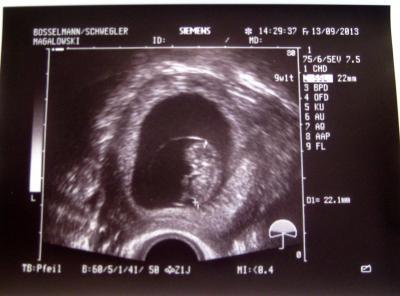

Soooooo endlich durfte ich auch zu einem Arzt, der endlich ein Ultraschall gemacht hat :) Krümelchen ist kerngesund, winkt und strampelt fleißig, das Herzchen blubbert - alles so wie es in der 10. Woche sein soll :) ET ist immernoch der 13.04.

Schön das alles gut ist! Da sieht man ja schon richtig Arme und Beine! Ich hab am Dienstag Termin, auch in der 10. Woche, ich hoffe dass ich dann auch so ein tolles Bild bekomme. LG popeye

Jaaaa als es sich bewegt hat, hat man Arme und Beine noch viel deutlicher gesehen, erst hat es geschlafen und dann meinte die Ärztin "oh schau mal, es bewegt sich" und dann wars ganz munter und hat gezappelt und "gehüpft" :) Mein kleiner Goldspatz, da hat sich das lange warten auf den ersten Ultraschall echt gelohnt.... Und das süßeste ist der dicke Bauch